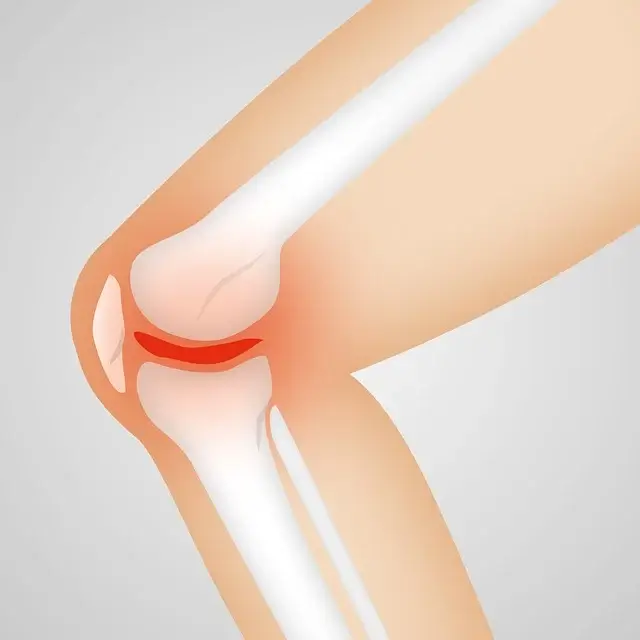

1) 우리의 무릎 관절 안쪽과 바깥쪽에 있는 반달 모양의 연골(반월상 연골)은, 무릎의 관절을 보호하고, 외부로부터의 충격을 흡수하거나 분산하는 역할을 해야 합니다. 그런데 반월상 연골이 그 역할을 감당해내지 못하면서 무릎을 구부릴 때 통증이 발생하게 됩니다

3) 무릎 연골은 무릎의 위쪽 뼈와 아래쪽 뼈의 충격이나 마찰을 줄여주는 역할을 합니다. 그런데 연골이 손상되어 닳아 없어지면서 무릎을 구부릴 때 뼈와 뼈가 서로 맞붙으면서 통증을 일으킵니다